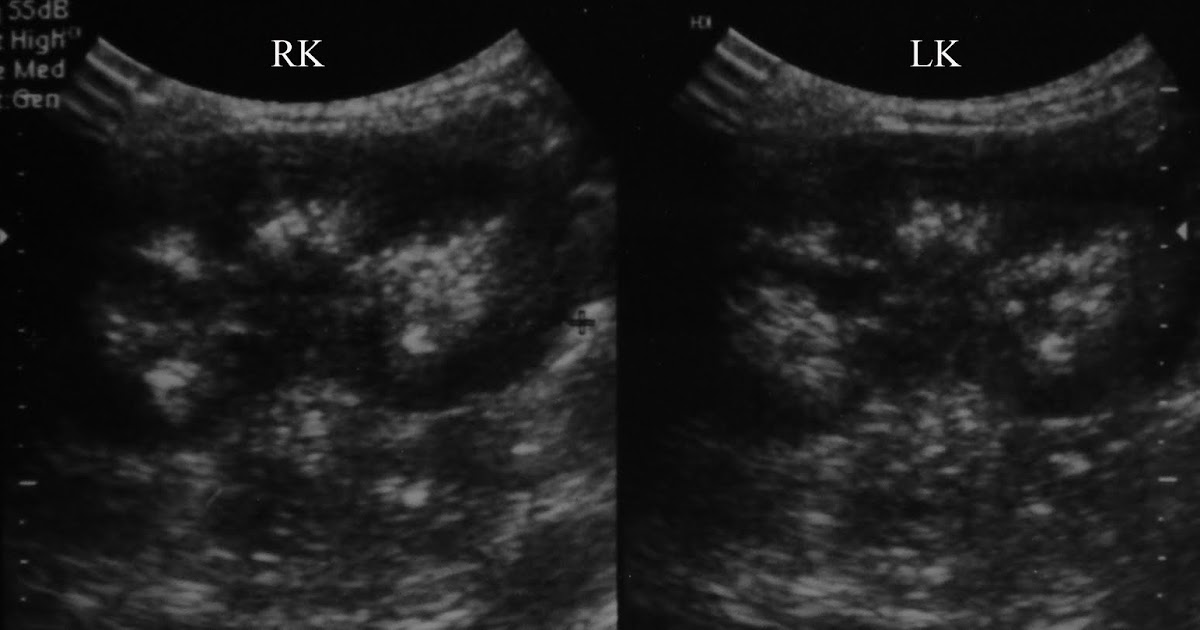

Medullary nephrocalcinosis Ultrasound Sumer's Radiology Blog

Medullary nephrocalcinosis radRounds Radiology Network Medullary Sponge Kidney Vs Nephrocalcinosis nephrocalcinosis is the deposition of calcium salts in the kidney parenchyma and tubules. medullary sponge kidney is a condition where the collecting ducts are dysplastic and dilated, often causing. medullary sponge kidney without calcifications may appear. distinguishing medullary sponge kidney from medullary nephrocalcinosis is important. Medullary sponge kidney is one of. learn about the causes,. Medullary Sponge Kidney Vs Nephrocalcinosis.

Medullary nephrocalcinosis Ultrasound Sumer's Radiology Blog Medullary Sponge Kidney Vs Nephrocalcinosis medullary sponge kidney (msk) disease is a rare condition affecting the distal nephron within the renal medulla. medullary sponge kidney is a condition where the collecting ducts are dysplastic and dilated, often causing. medullary sponge kidney (msk) is a congenital disorder resulting in ectatic collecting ducts within one or both. medullary sponge kidney without calcifications may. Medullary Sponge Kidney Vs Nephrocalcinosis.